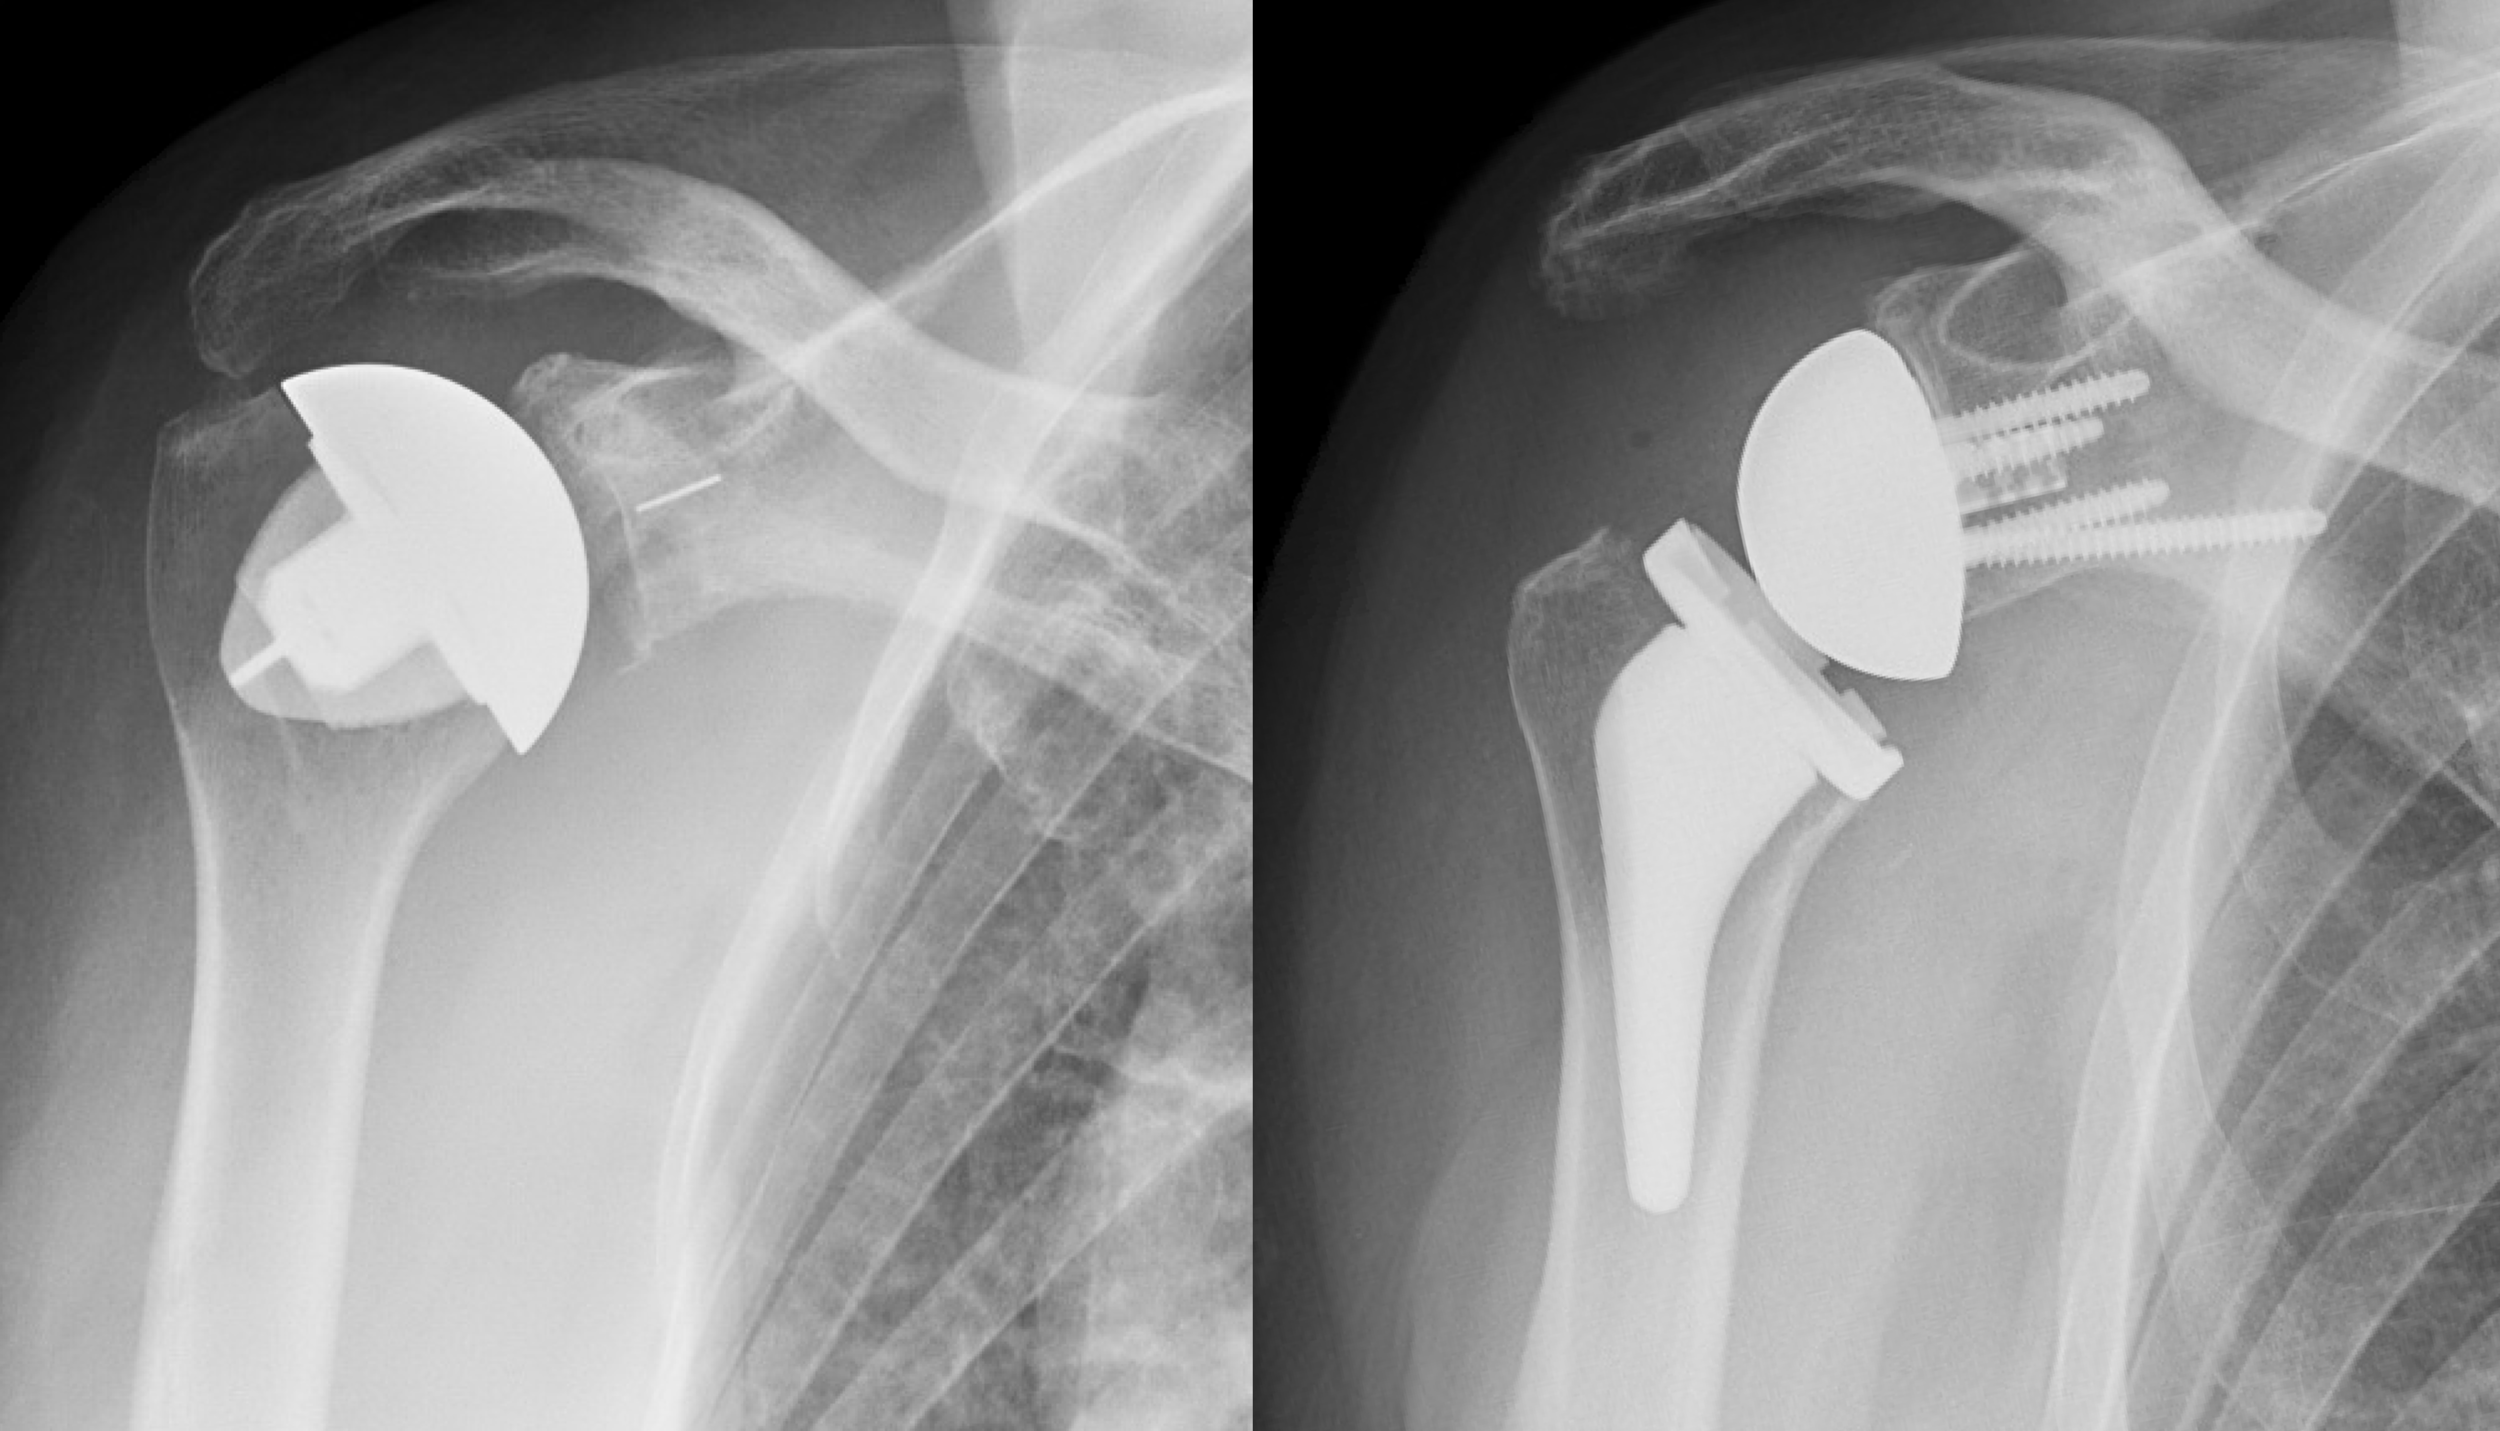

In these instances, a doctor may suggest diagnostic imaging, such as an X-ray or MRI, to rule out structural issues like a herniated disc or nerve impingement. Physical therapy, chiropractic care, or specialized pain management programs can provide targeted support that far exceeds general home remedies.